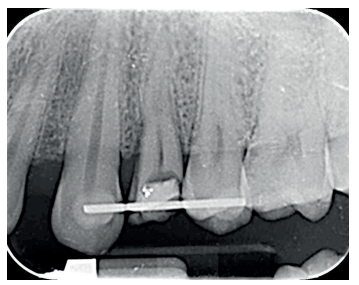

Se presenta en el Máster en Cirugía Oral, Implantología y Periodoncia de la Universidad Alfonso X El Sabio (Madrid, España) un paciente de 24 años derivado para exodoncia del primer premolar superior izquierdo y colocación inmediata de implante debido a una fractura corono-radicular como consecuencia de caries asintomática, con margen distal 2 mm subgingival y limitada estructura remanente (Figuras 1 y 2). Después de un estudio completo del caso, en colaboración con el Máster en Endodoncia de la misma facultad, se planificó la realización de la extrusión quirúrgica, endodoncia y posterior rehabilitación del diente. Dentro de este estudio resultaron de vital importancia las pruebas radiológicas, compuestas por radiografías periapicales y CBCT, que confirmaron la compatibilidad de la anatomía radicular con la realización de una extrusión mínimamente traumática.

con fractura corono-radicular.

fractura corono-radicular.